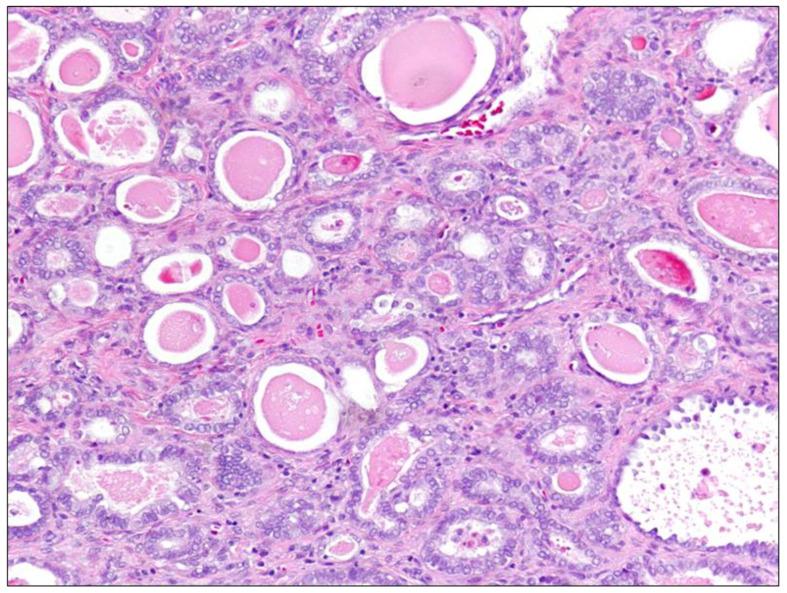

Cervical cancer (CC) is the fourth most frequent cancer in women worldwide. HPV infection is associated with the majority of CC cases, but a small proportion of CCs actually test negative for HPV. The prevalence of HPV among CC histotypes is very different. It has been suggested that HPV-negative CC may represent a biologically distinct subset of tumors, relying on a distinct pathogenetic pathway and carrying a poorer prognosis, than HPV-positive CCs. Although, the discordance in terms of sensitivity and specificity between different HPV tests as well as the potential errors in sampling and storing tissues may be considered as causes of false-negative results. The identification of HPV-negative CCs is essential for their correct management. The aim of this narrative review is to summarize the clinical and pathological features of this variant. We also discuss the pitfalls of different HPV tests possibly leading to classification errors.

宫颈癌(CC)是全球女性中第四常见的癌症。人乳头瘤病毒(HPV)感染与大多数宫颈癌病例相关,但实际上有一小部分宫颈癌HPV检测呈阴性。HPV在宫颈癌组织学类型中的流行率差异很大。有人提出,与HPV阳性宫颈癌相比,HPV阴性宫颈癌可能代表生物学上不同的肿瘤亚群,依赖于不同的致病途径,预后较差。尽管如此,不同HPV检测在敏感性和特异性方面的不一致以及组织采样和储存中的潜在误差可能被视为假阴性结果的原因。识别HPV阴性宫颈癌对于其正确管理至关重要。本叙述性综述的目的是总结该变体的临床和病理特征。我们还讨论了可能导致分类错误的不同HPV检测的陷阱。